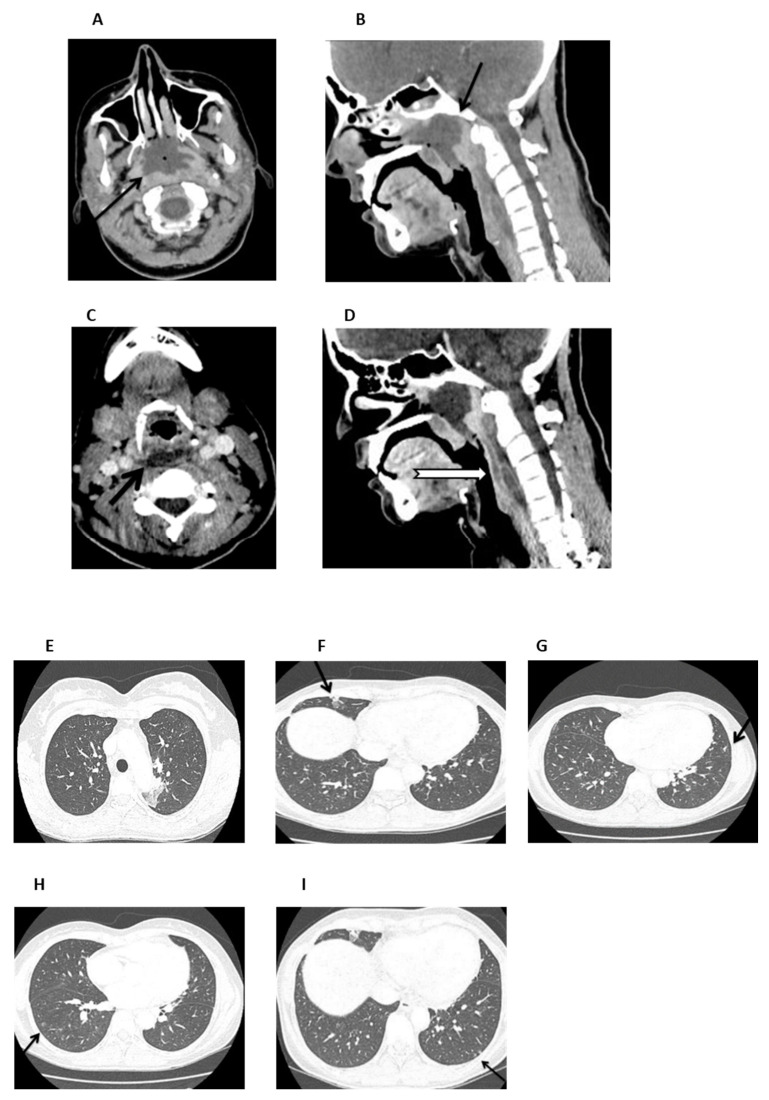

Case report: We describe a case of a 36-year-old female patient diagnosed with SAA, for whom IST was considered, due to the unavailability of a matched sibling donor for HSCT. The patient presented with a feverish condition and deep neck space abscesses were revealed by imaging, caused by invasive aspergillosis. To prioritize infection control, IST was postponed and antifungal therapy with abscess drainage was initiated. However, aspergillosis progressed, despite aggressive and prompt treatment, and ultimately resulted in sepsis, multiorgan failure, and death. In addition, mucormycosis was confirmed post-mortem. Two heterozygous PRF1 polymorphisms (c.272C>T and c.900C>T), were identified by genetic testing, which may have contributed to immune dysregulation and fungal dissemination.